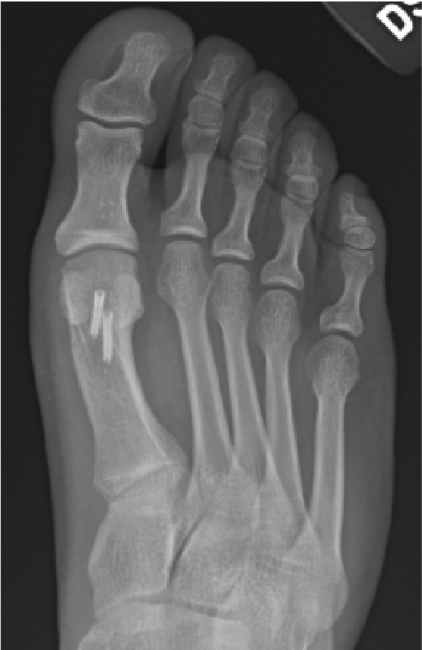

There have been several review papers that looked at staging and various classifica-tion systems, and none ever takes into account chondromalacia. I have shown many cases over the years where systems would classify patients as Stage I, but in reality, they had significant full-thickness defects of the metatarsal head, as shown in Figure 1. Despite little to no osteophytes, many athletes will have adequate dorsiflexion without pain. Pain only existed with activity and weightbearing. None of the classification systems takes into account sesamoid position, which is crucial for predicting potential crista damage.

Either way, the multiple classification systems available should not be utilized alone to determine surgical treatment. More often I find that these systems ignore instability, elevation, or metatarsal length. As some studies concluded, classification failed to correlate with every patient.7,8 Roukis and colleagues in 2002 presented his four-stage radiographic analysis—which finally incorporated some radiographic measurements to include metatarsal protrusion, intermetatarsal angle, and talo-first metatarsal angles—which looks at elevatus, as shown in Figure 2 above and Figure 3 below.9 He then followed that up with an article on metatarsus primus elevatus in 2005.10 Then Elliott and colleagues’ 2016 follow-up review11 on Roukis’s 2002 study9 concluded that regardless of the etiology or surgery performed, patients were happier; however, their ROM never improved.

long history of plantar fasciitis. B. The below X-ray shows elevation, with the first metatarsal head not even touching the floor.